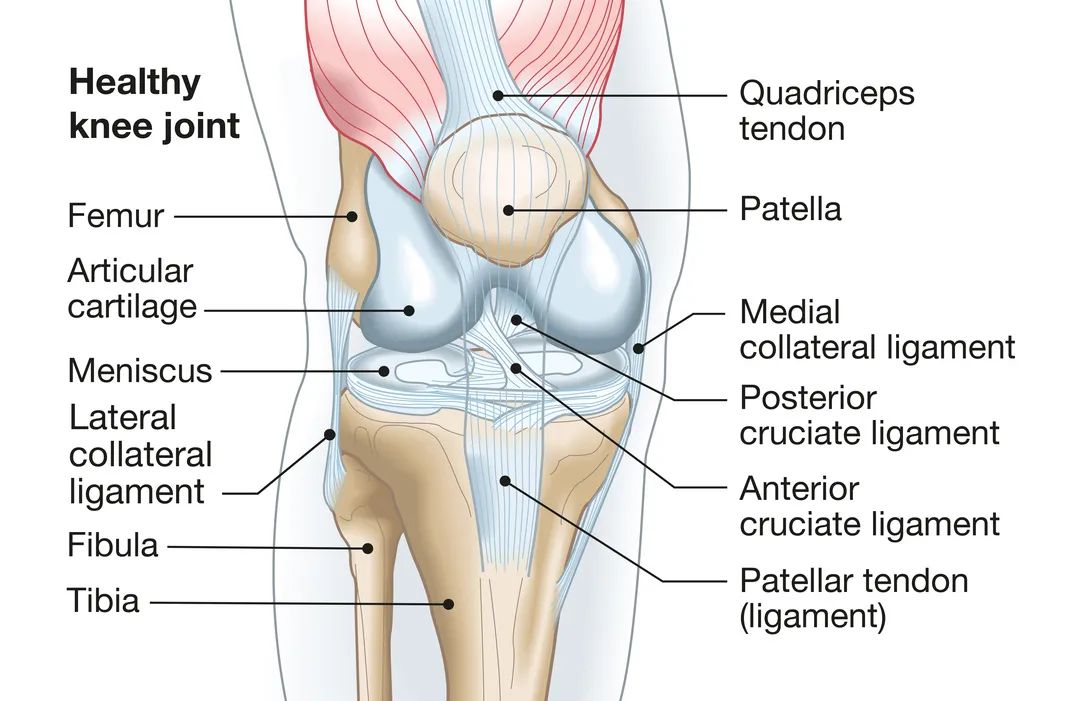

养关节其实就是在养软骨。关节软骨虽然仅有几毫米厚,但其结构与成分却十分精致。它们覆盖在骨骼上,主要由胶原纤维组成。关节软骨就像车子的避震器,又类似一块分层的海绵,各层之间通过微小的位移,来缓解关节活动时产生的磨损和震荡。

关节软骨不含血管、淋巴管和神经,因而其代谢所需营养全靠关节的滑液维持。关节在运动中间断受压,有益于滑液进出软骨;如关节损伤,软骨将因缺乏营养交换而萎缩、软化,甚至退变。

骨关节炎会使关节中的软骨变得僵硬并失去弹性,使其更容易受到损伤。久而久之,软骨的某些区域会发生磨损,由光滑如境变得粗糙不堪,摩擦系数大大增加,减震作用大幅降低。随着软骨磨损,肌腱和韧带拉伸,就会引起疼痛。